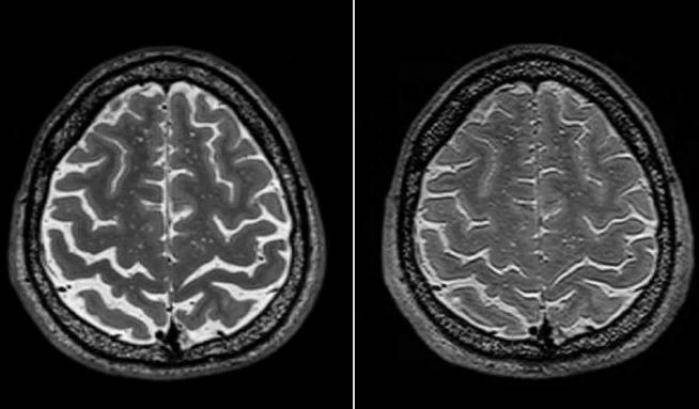

Cosa accade al cervello degli astronauti nello spazio? Questa domanda è oggetto di continue ricerche da parte degli scienziati. Un nuovo studio, condotto da un team di ricercatori guidato da Donna Roberts, neuro-radiologa alla Medical University of South Carolina, ha indagato ulteriormente sui cambiamenti che potrebbe subire la struttura cerebrale degli astronauti durante la permanenza nello spazio – ne abbiamo parlato qui per la prima volta. Come sappiamo, l’esposizione prolungata ad un ambiente di microgravità ha effetti permanenti sugli esseri umani, che ancora non riusciamo ancora a comprendere a pieno. Il team ha esaminato i dati delle risonanze magnetiche di 19 astronauti Nasa, osservando cambiamenti strutturali diffusi nel cervello, specialmente dopo missioni di lunga durata. Questi cambiamenti sembrano essere correlati alle variazioni nelle capacità motorie degli astronauti e nelle loro prestazioni cognitive durante i test post-volo.